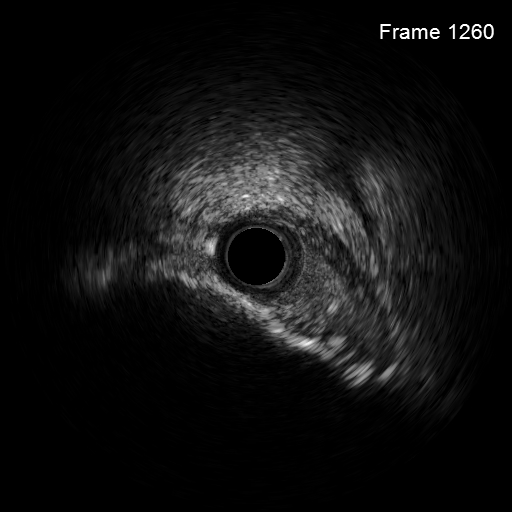

考虑到患者钙化严重且弥漫,为精准化钙化病变预处理方案,对患者进行IVUS检查,但超声导管无法通过病变部位;

病变部位旋磨后,振波后超声对比